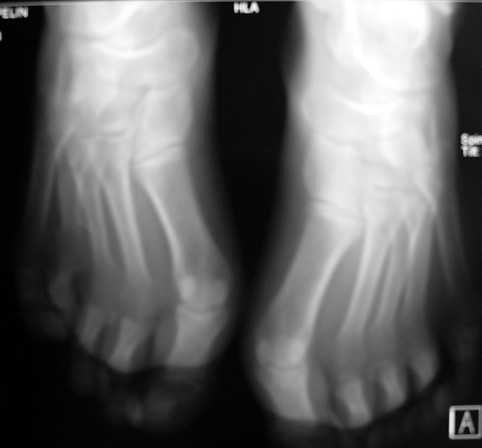

El parmağı (metakarp) ve ayak parmağı (metatars) kısalıkları doğuştan tek başına, geniş bir sendrom grubuyla birlikte, travma sonrası, Freiberg hastalığı (avasküler nekroz) sonrası görülebilir.

Doğuştan metakarp ve metatars kısalığının görülme sıklığı 1/1000’den azdır. Kadınlarda erkeklere göre 5 kat daha fazla görülür ve sıklıkla (%72) iki taraflıdır. En sık 4. parmak tutulur. Bu tür olgularda sorunun nedeni tam olarak bilinmemekle brlikte deformitenin genellikle epifiz plağının erken kapanmasından kaynaklandığı düşünülmektedir.

Metakarp kısalığında kozmetik görünümün bozulması ve dominant elin kullanımı sırasında yorulma, metatars kısalığında ise kozmetik haricinde metatarsalji, kısa parmağın dorsale kayması sonucu deformite oluşması, plantar yönde açılanması sonucu ağrı ve bası ülserleri, ve ayakkabı giymede zorluk nedeniyle ameliyat gerekebilir.